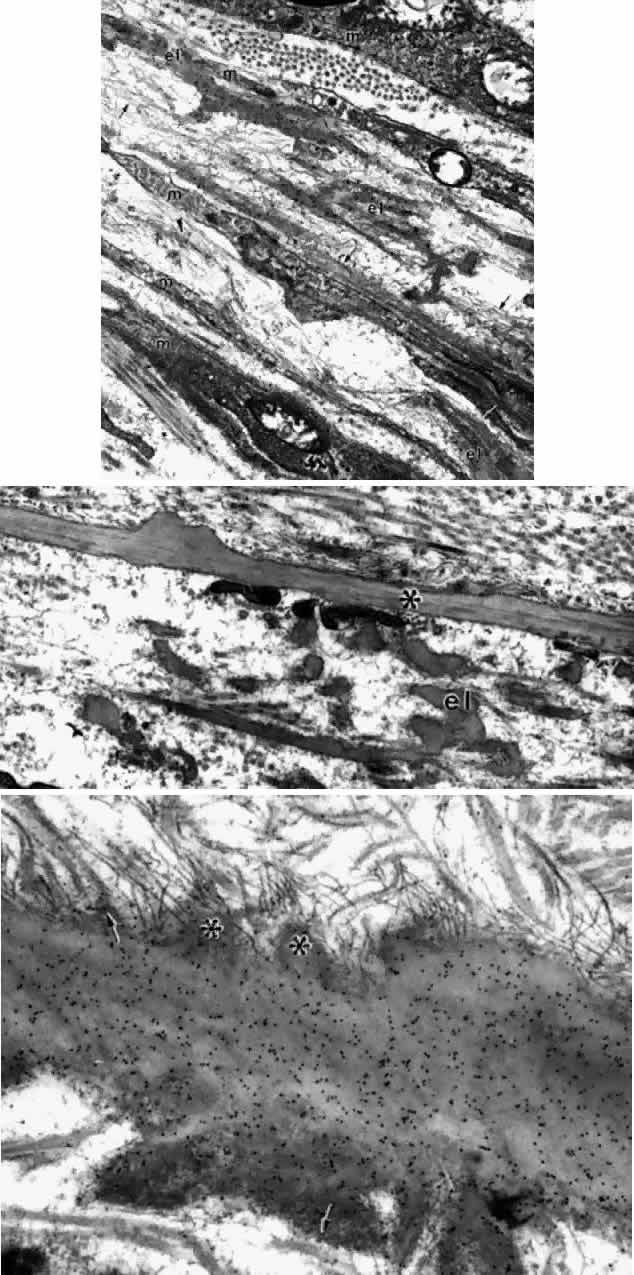

Fig. 16. Ciliary epithelium in the anterior pars plicata of a 19-year-old. Posterior

chamber surface (PC) of the nonpigmented epithelium (NPE) has a sawtooth

pattern seen irregularly throughout this layer with aging. Mitochondria (m) are

large, plentiful, and show artifactual hydropic change. Rough

endoplasmic reticulum is present below the nuclei (asterisk). Note

that the apices of the pigmented epithelial cells (PE) are conical, with

prolongations of NPE between them. (X 8320) Fig. 16. Ciliary epithelium in the anterior pars plicata of a 19-year-old. Posterior

chamber surface (PC) of the nonpigmented epithelium (NPE) has a sawtooth

pattern seen irregularly throughout this layer with aging. Mitochondria (m) are

large, plentiful, and show artifactual hydropic change. Rough

endoplasmic reticulum is present below the nuclei (asterisk). Note

that the apices of the pigmented epithelial cells (PE) are conical, with

prolongations of NPE between them. (X 8320)

In the pars plana, the tall NPE cells have numerous intermediate filaments

and granules that give the cells a more electron-dense appearance

than anteriorly (Fig. 18A) and are profusely supplied with tubules of smooth-surfaced endoplasmic

processes.  Fig. 18. Posterior pars plana. A. Nonpigmented epithelial (NPE) cells appear tilted

and compressed with dense cytoplasm. The extensive cystic dilatation

of the intercellular spaces (IS) around these cells is characteristic

of this region. Only the nucleus (N) and the many hydropic mitochondria

are visible in the cytoplasm. The basement membrane under the pigment

epithelium (PE) is multilaminarand thick. (X 5700) B. Higher magnification

of asterisked region in A shows that the cytoplasm is full of

branching and curved profiles of smooth endoplasmic reticulum (arrow), which

is also typical of this region. M, mitochondrion. (X 22,000) Fig. 18. Posterior pars plana. A. Nonpigmented epithelial (NPE) cells appear tilted

and compressed with dense cytoplasm. The extensive cystic dilatation

of the intercellular spaces (IS) around these cells is characteristic

of this region. Only the nucleus (N) and the many hydropic mitochondria

are visible in the cytoplasm. The basement membrane under the pigment

epithelium (PE) is multilaminarand thick. (X 5700) B. Higher magnification

of asterisked region in A shows that the cytoplasm is full of

branching and curved profiles of smooth endoplasmic reticulum (arrow), which

is also typical of this region. M, mitochondrion. (X 22,000)